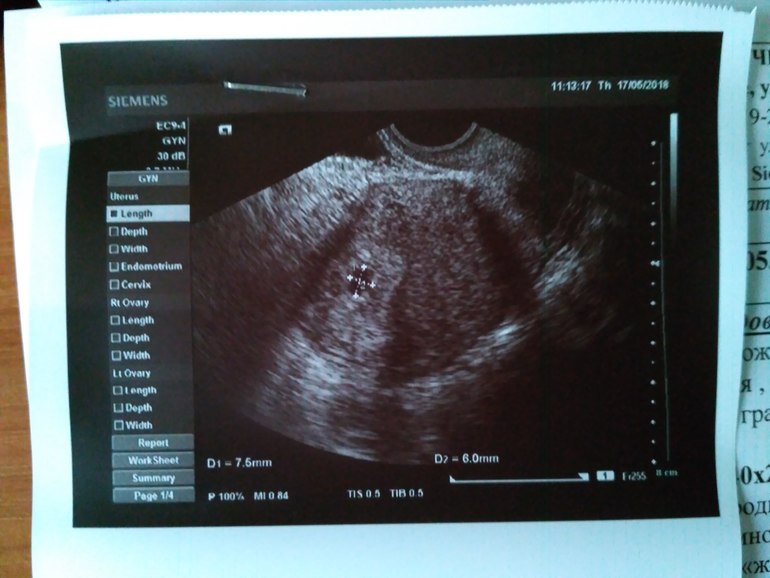

Всем привет, вчера была на осмотре и на УЗИ.

Сегодня была у гинеколога и на УЗИ. Все отлично, тонуса нет, ровные контуры. И тут как гром среди ясного неба... Прогестерон 5,68.

Всем привет, сходила я сегодня к гинекологу, срок 5 недель и 2 дня. Все хорошо, плодное яйцо в матке. Гинеколог подтвердила что беременность маточная, но зная какая я мнительная отправила на УЗИ) увидела я бусинку❤ узист тоже ставит срок 5-6 недель. Сдал...